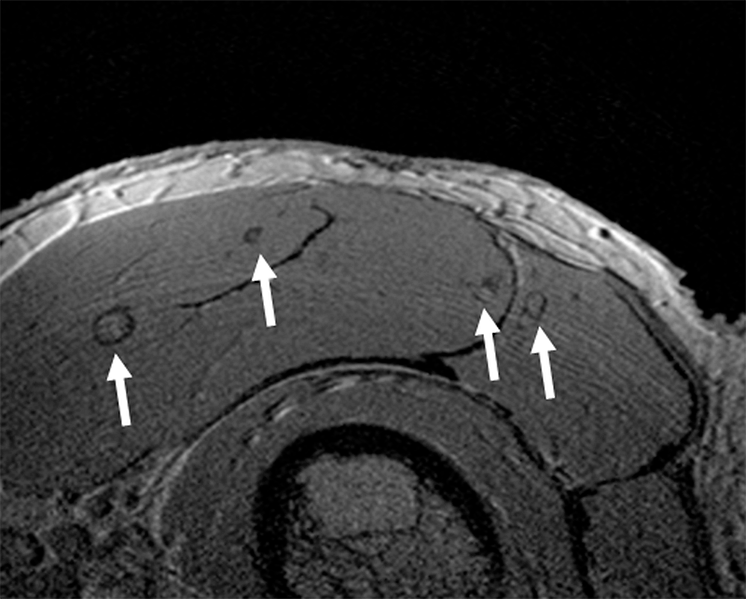

Tvärsnitt genom en muskel på underarmen hos en 66-årig patient tre månader efter transplantation av Langerhanska öar (Dr Johan Permert, Karolinska universitetssjukhuset, Huddinge). Pilarna visar ett tvärsnitt av öarna i muskeln. Tekniken för framställning av bilden har utvecklats vid MR-sektionen, Enheten för radiologi, Akademiska sjukhuset.